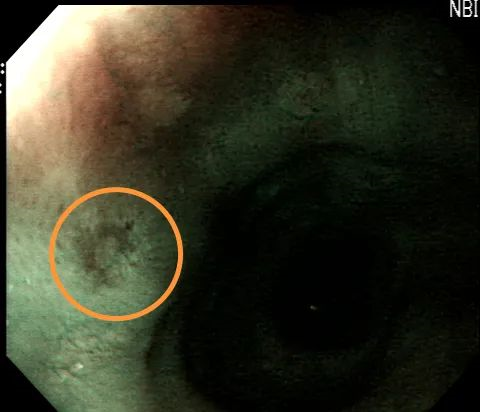

食管NBI观察

NBI作为一种新兴的内镜技术,是目前该领域尖端的诊断技术,具备高清晰成像功能,附带NBI功能的变焦放大内镜,在对病灶近距离放大观察后再开启NBI模式,能更清晰地了解病灶表面的黏膜凹窝形态及血管等,能够发现普通内镜难以发现的食道、胃、十二指肠等早期病变,在食道、胃、十二指肠等恶性肿瘤的早期诊断方面具有重要的临床价值。